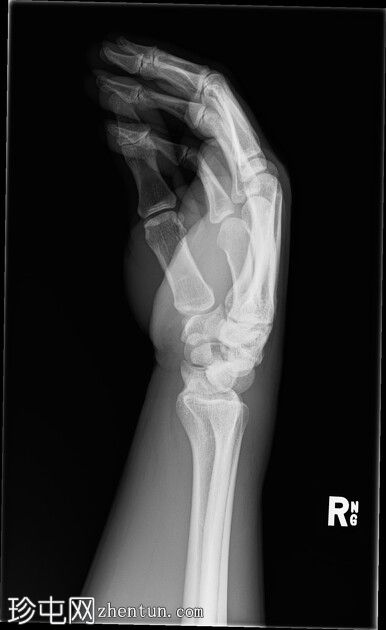

右腕

X光片

正面

斜位

侧面

前后位:舟月骨间隙增宽,月骨呈三角形。侧面显示头状骨与月骨背侧脱位,月骨与桡骨远端保持正常排列。符合月骨周围脱位的特征。无合并腕骨、桡骨或尺骨骨折。腕部软组织肿胀。